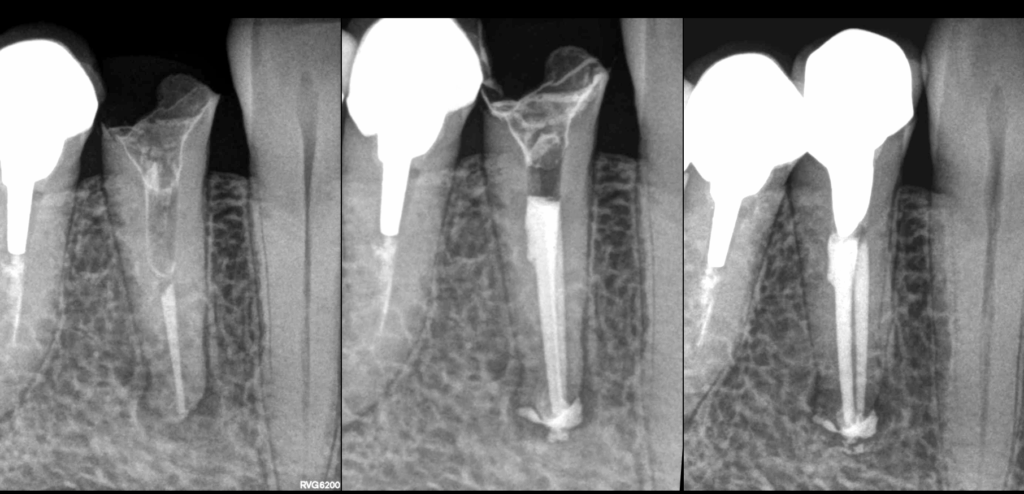

🔍 Dent 44 adressée pour inefficacité du traitement canalaire du point de vue l’environnement osseux.

3️⃣ Parce qu’un canal n’avait pas été traité

👉 ✅ 𝐎𝐮𝐢 : 𝐥𝐞 𝐜𝐚𝐧𝐚𝐥 𝐋.